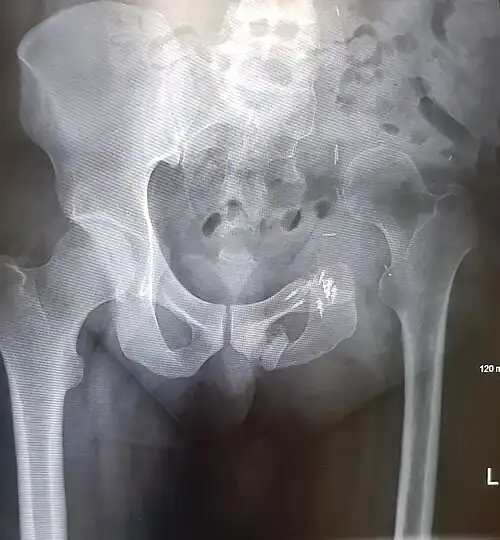

An x-ray of a limb-sparing hemipelvectomy on the left side of a male pelvis taken one month after surgery. -